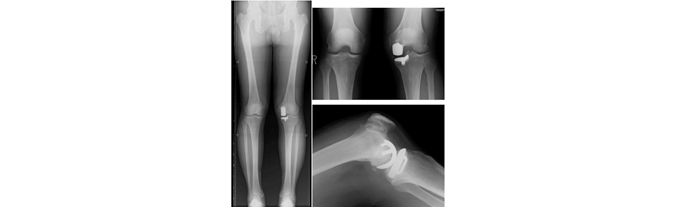

膝の内側の軟骨がすり減って徐々にO脚が進行してゆく変形性膝関節症があります。我が国での変形性膝関節症の推定患者数は、1700万人にのぼると言われております。

我々は、変形性膝関節症に対して関節温存手術を検討する場合、患者さんの下肢アライメント解析を行い、それぞれの変形に応じて種々の骨切り術(open wedge 型高位脛骨骨切り術、closed wedge 型高位脛骨骨切り術、大腿骨遠位骨切り術、脛骨顆外反骨切り術)を駆使し、治療にあたっております。関節鏡も併用し、骨髄刺激法や半月板縫合など、適宜処置を追加します。

壊れた関節の部分だけを金属とポリエチレンに置換します。

加齢や関節リウマチ、外傷などの原因により高度に障害された関節表面を取り除き、関節部分を金属とポリエチレンに入れ替える手術です。ポリエチレンでできた部分が軟骨の役割を果たし、滑らかに人工関節が動くことができます。

障害された膝関節は人工関節に置換することで痛みが大きく和らぎ、滑らかな動きができるようになり、歩きやすくなります。また、関節の変形も矯正されます。人工膝関節置換術は日常生活の質を高める治療効果の高い手術であると言えます。